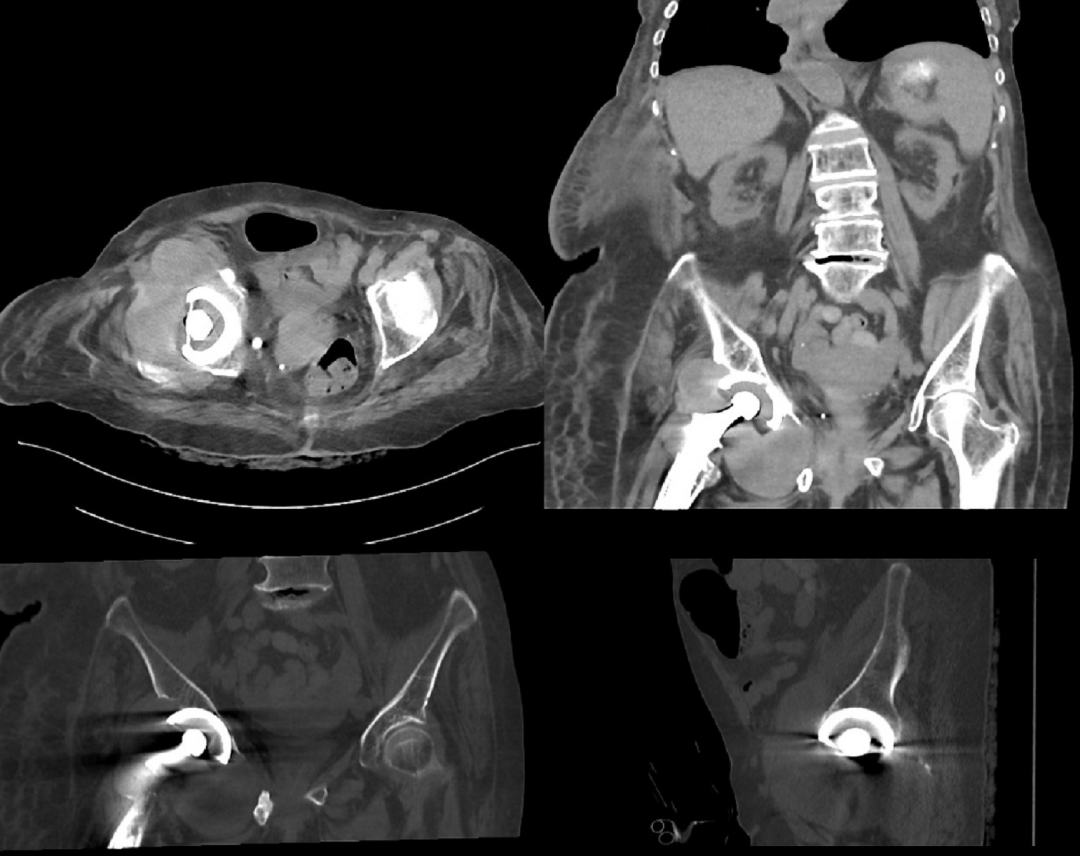

5. Metal-on-metal(MOM)disease:

假性滑囊,是金属对金属髋关节置换的组织反应;表现为髋关节假体周围的滑囊。最常见的部位是:髋臼上缘、大粗隆和小粗隆。

人工髋关节置换术。假体周围囊性肿块(箭头)